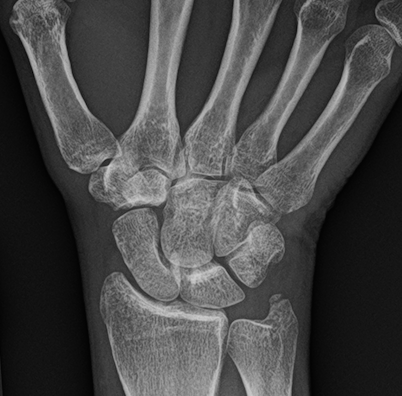

- This one-hour postgraduate lecture provides a focused, clinically relevant approach to the evaluation of wrist and hand pain and dysfunction. Emphasis is placed on functional and MRI anatomy, common mechanisms of injury, orthopedic examination strategies, and appropriate imaging utilization in both acute trauma and chronic conditions. Participants will learn to correlate examination findings with imaging features to improve diagnostic accuracy, recognize carpal instability patterns, identify red flags, and determine when conservative care versus referral is indicated.

- Carpal instability patterns, fractures, ligament injuries, and arthritides